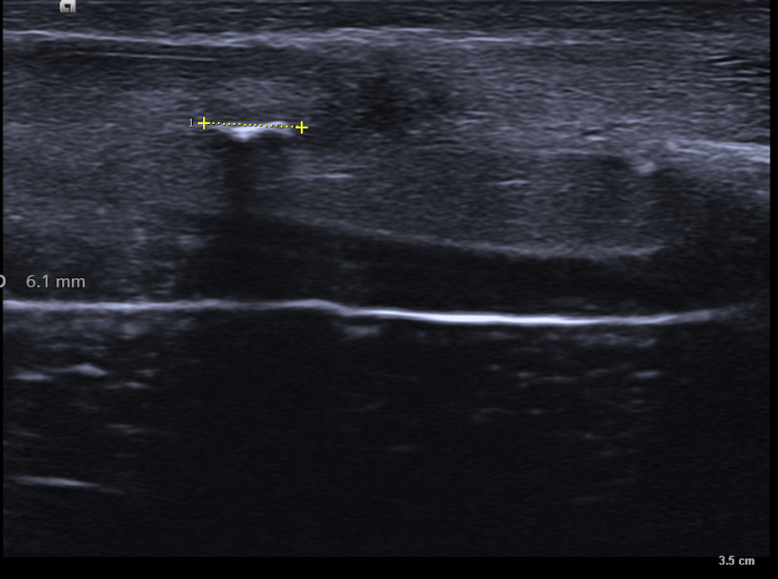

Estas tres próximas imágenes que vas a ver son tres claros ejemplos de lo que es una calcificación grosera de la túnica albugínea, mira:

En estas tres imágenes ves claramente una calcificación grosera, ligeramente curva, que afecta a la túnica albugínea del cuerpo cavernoso izquierdo en su porción interna y profunda. Mide algo menos de 7 mm y esto ya se considera una placa bastante grande. El paciente, por cierto, no cumplía con los estándares de incidencia habitual, tenía menos de 40 años.